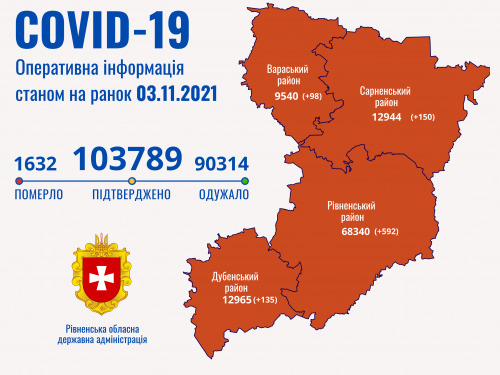

Пів тисячі - у важкому стані, 9 жителів Рівненщини померли за добу від коронавірусу